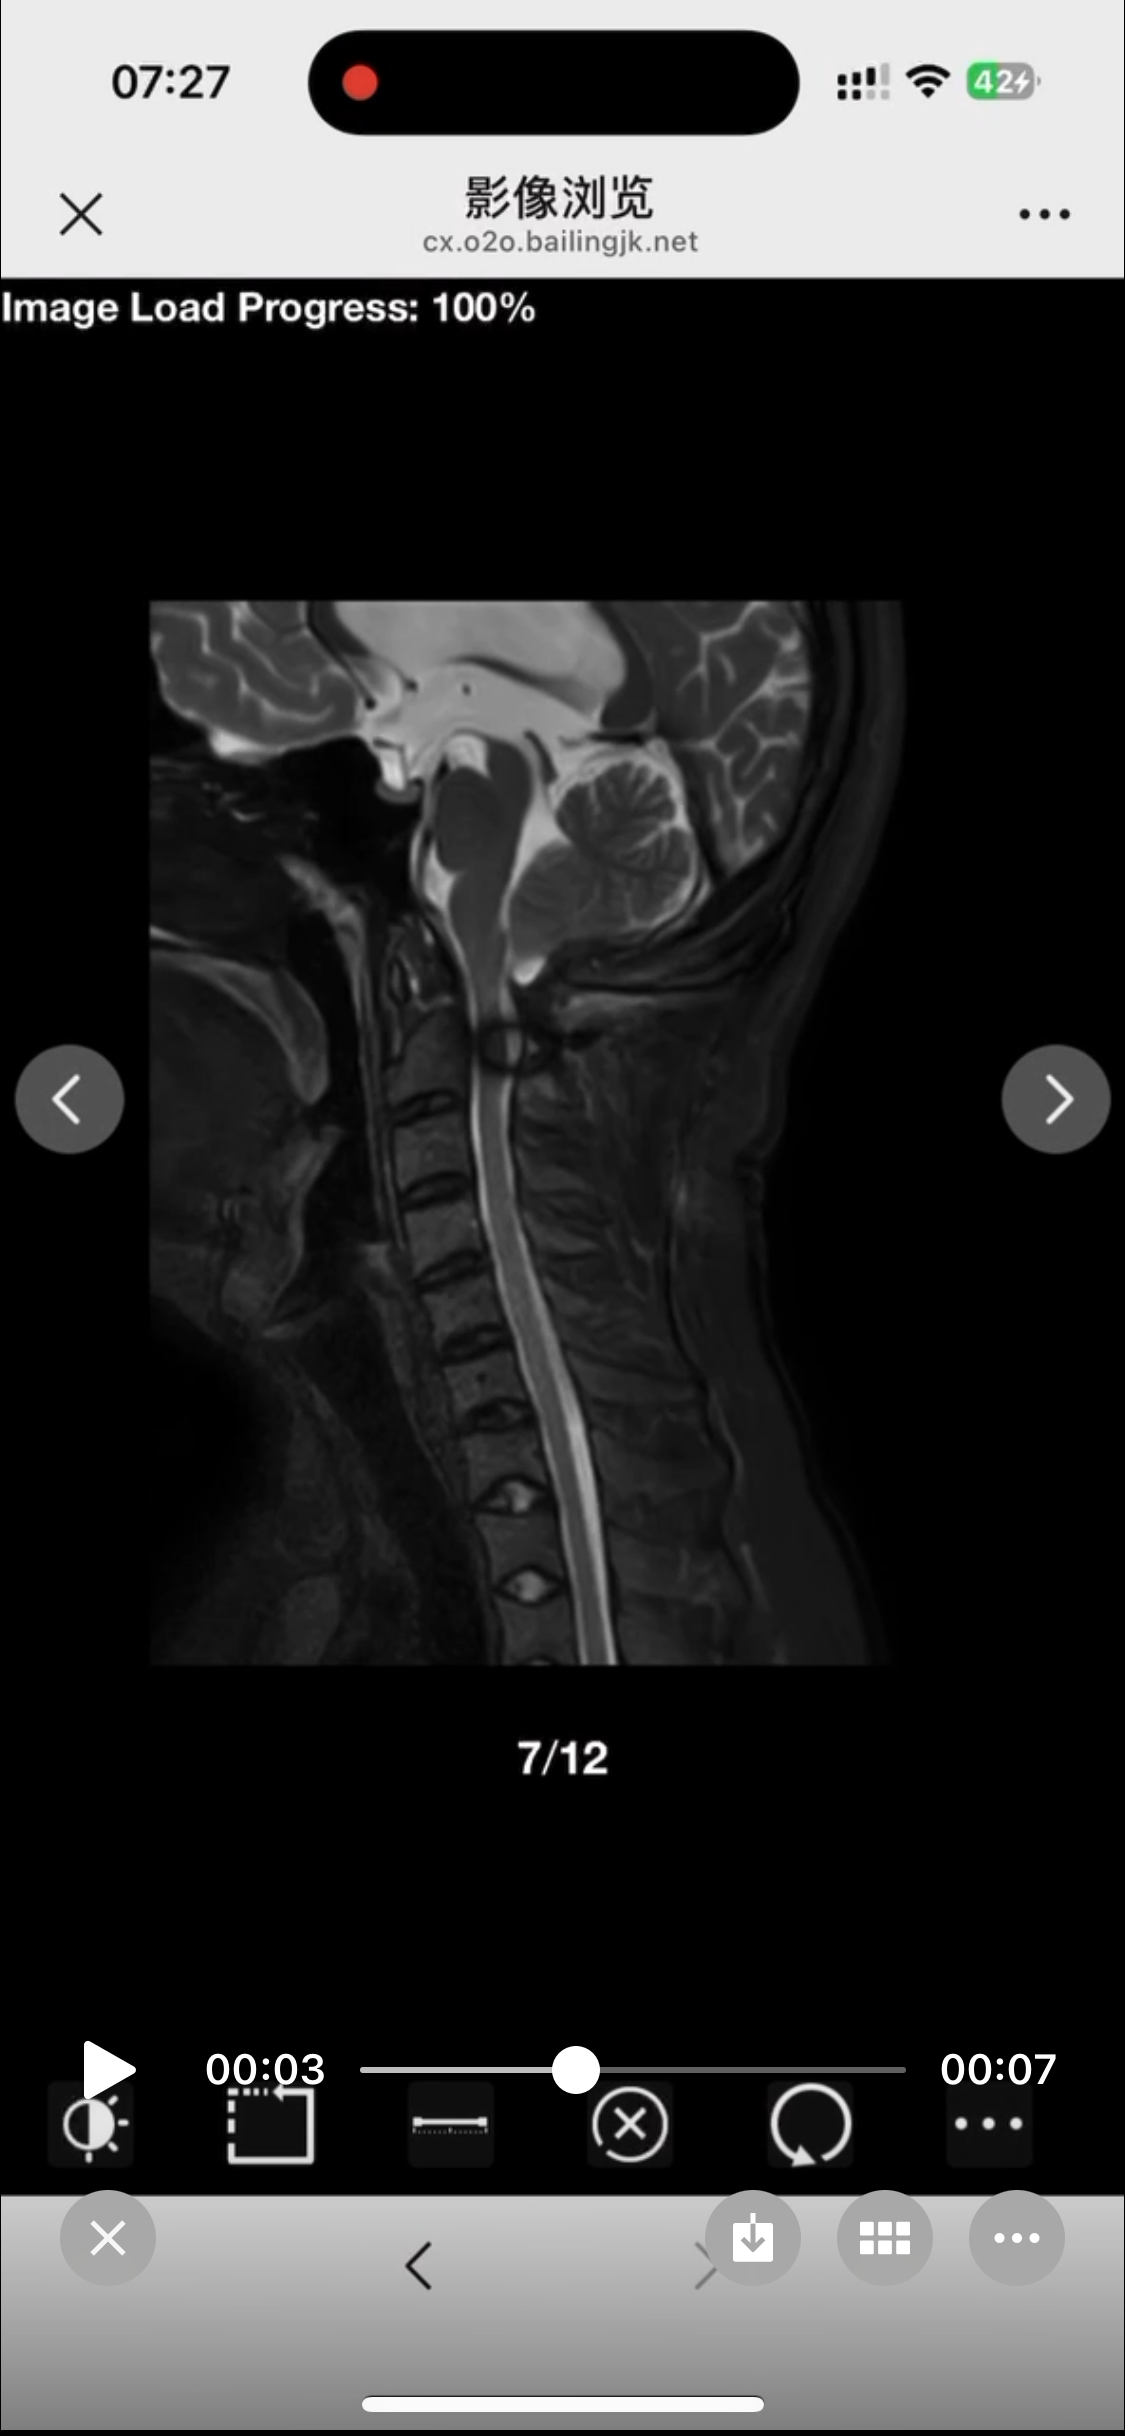

• 诊断:寰枢椎脱位

• 影像:

• 术后状况:术前患者同意不放融合器,术中切了后宫,术后复位还不错

• 术后影像: